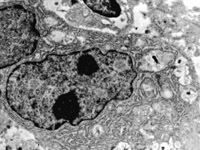

5-2-8 伤后第10天,皮肤附件上皮细胞成簇分布,核仁边集,内质网扩张,胞质内含较多张力原纤维 TEM×6000